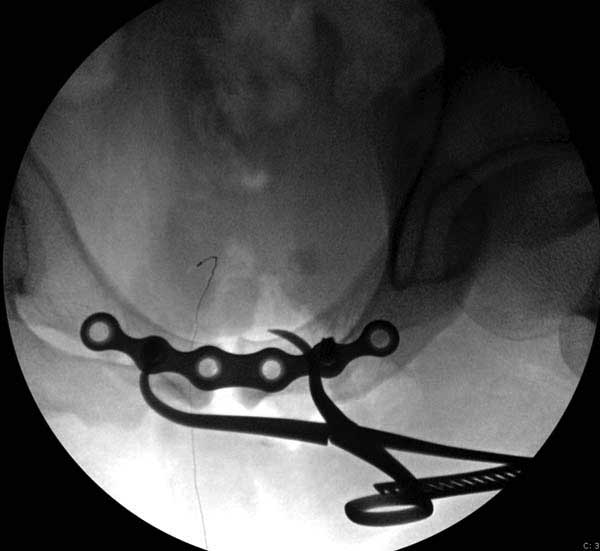

Представлены снимки техники проведения стержней. Через место прикрепления прямой мышцы в Inferior Iliac Spine в направления вырезки создается жесткость. Weber clamp изнутри таза для репозиции, и фиксация после репозиции перелома крыла подвздошной кости. Наружный аппарат удален, нагрузка предполагается через два месяца.